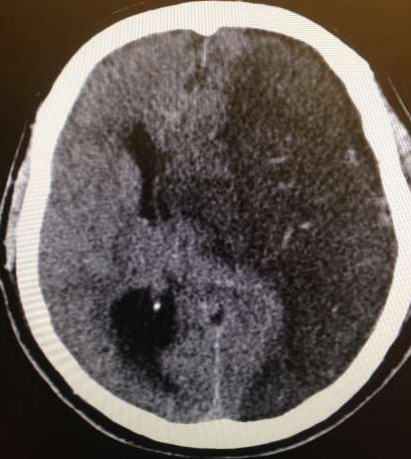

The CT brain, performed on arrival and showed acute left -sided distal MCA occlusion with a small core and large surrounding penumbra (Fig. 1.). The cause was thought to be cardioembolic in nature.

Fig. 1. Computer generated map showing a left -sided MCA infarction with midline shift of about 8 mm.

CT showed infarction of the right side which progressed to paresis whilst on transfer to stroke unit for further management

Fig 3: CT Brain showed a new right Middle cerebral artery MCA infarction.